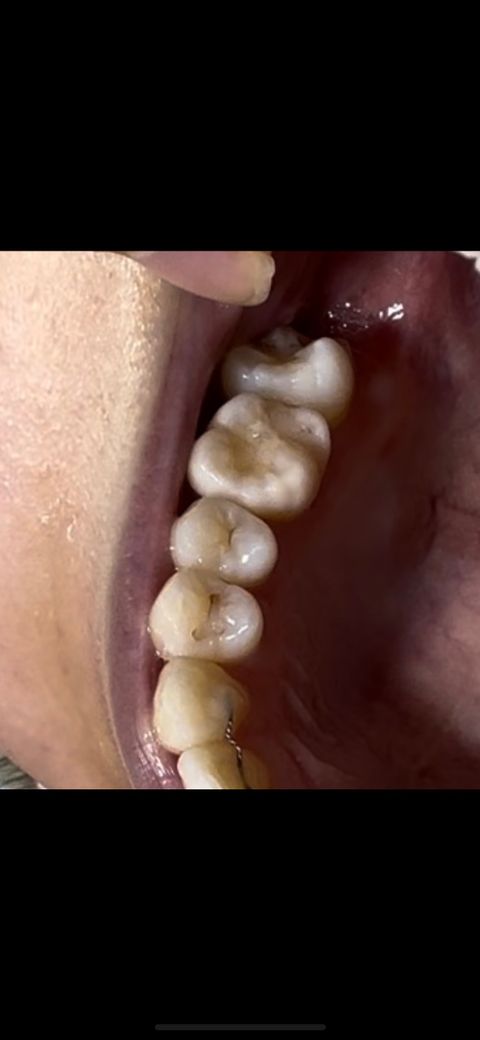

이거 2차충치인가요..? 레진이였습니다

충치 레진으로 치료한지 한 8년정도 지났습니다

레진 부분이 선으로 저렇게 변색된 부분이 존재하는데 그냥 변색된건가요 아니면 2차충치인가요..?

충치라면 많이 심한건가요?? 어느정도 치료를 받아야하는지 알려주세요

• 1번 째 사진